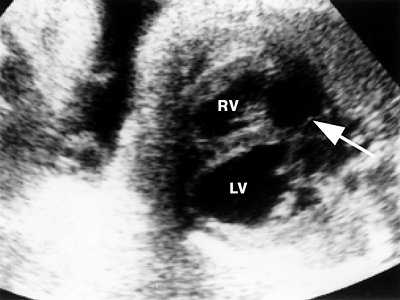

Четвертое наблюдение. Беременность 34 недели. При ультразвуковом исследовании у плода диагностирована фиброэластическая форма кардиомиопатии. Левый желудочек представлен шарообразной конфигураций с плотным светящимся эндокардом (рис. 6).

Рис. 6. Четырехкамерное сечение сердца плода. Фиброэластическая форма кардиомиопатии. Полость левого желудочка (LV) увеличена и имеет округлую форму, стенки уплотнены. Овальное окно не функционирует (стрелка), RV - правый желудочек.

Имеются признаки сердечной недостаточности: гепатомегалия и выпот в перикарде. Фиброэластический процесс распространился на межпредсердную перегородку, вызвав преждевременное закрытие овально го окна.